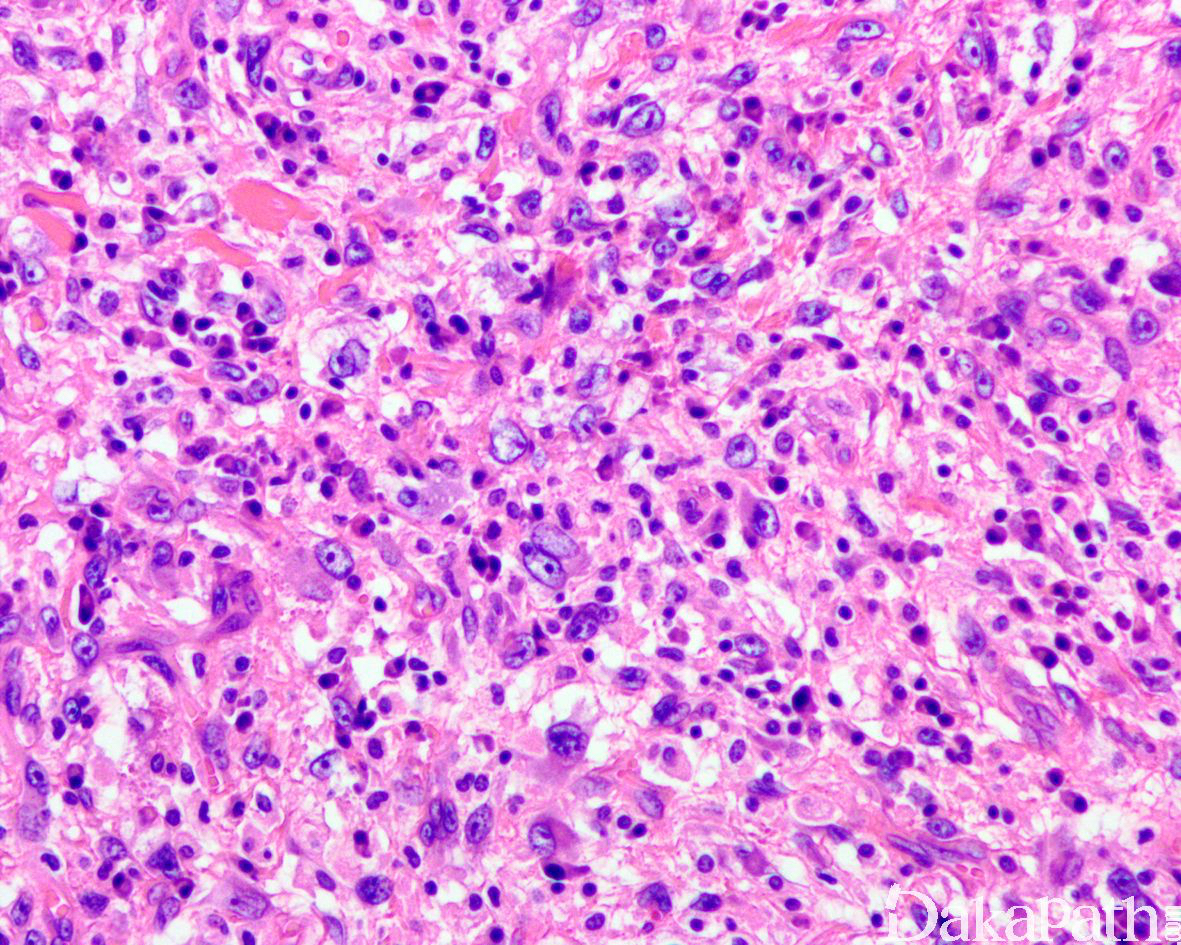

如前所述,DDLPS 组织学上通常表现为 ALT/WDLPS 成分向非脂肪源性的肿瘤成分转化,2 种成分在镜下通常分界较清楚,表现为突然的过渡;但有时可表现为逐渐的过渡或在整个肿瘤内交错的分布(马赛克样的去分化),这一情况尤其在伴有低级别去分化时常见。肿瘤可能部分带假包膜或边界清楚,但至少局部可见推挤状或浸润性边界,后腹膜的 DDLPS 常见累及周围实质器官(如肾脏等)。高分化与去分化成分的比例在不同肿瘤内多少不等,有时候即使在广泛取材的情况下高分化成分也可能完全确如,而去分化成分通常较广泛,但有时也可能仅仅不足 1 cm(又称为微小去分化)。DDLPS 中的 ALT/WDLPS 组织学类型以脂肪瘤样和硬化性为主,而去分化成分大多数表现为高级别去分化特征包括高级别多形性肉瘤样(多形性瘤细胞伴有席纹状排列类似于多形性未分化肉瘤/恶性纤维组织细胞瘤)、高级别梭形细胞肉瘤样(细胞密度较高的梭形瘤细胞伴有交错束状或鱼骨样排列类似于纤维肉瘤)以及少见的高级别圆细胞肉瘤样(弥漫的小蓝圆细胞类似于骨外尤文肉瘤或差分化的滑膜肉瘤)和上皮样特征(弥漫成片的上皮样瘤细胞伴有丰富的嗜酸性胞质或横纹肌样特征类似于转移性癌或恶性间皮瘤),高级别去分化成分通常瘤细胞密度高,间质稀少,核分裂象活跃(> 5 个/10 HPF),但比较于与之类似的肿瘤而言,去分化成分的核分裂象相对较少;坏死较为常见。